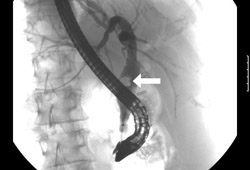

Acute cholangitis

Endoscopic retrograde cholangiopancreatography reveals a large common bile duct (CBD) stone (arrow) in the mid-common bile duct

From the collection of Douglas G. Adler; used with permission